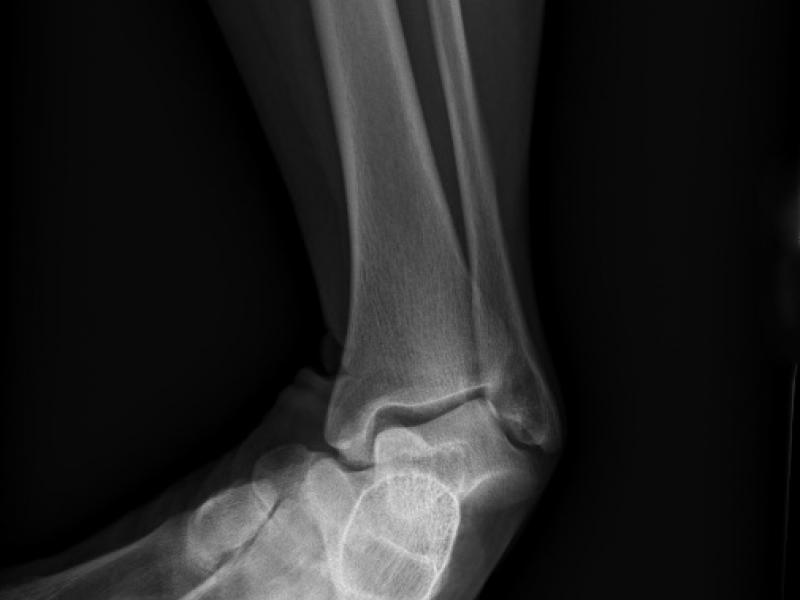

What's the diagnosis?  By Dr. F. Jon Skilton

A 60 yo female presents with ankle pain after a fall from a